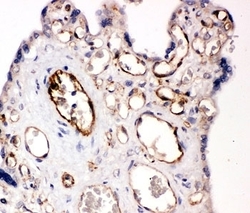

- Submitted by

- NSJ Bioreagents (provider)

- Main image

- Experimental details

- IHC-P: CD31 antibody testing of human placenta tissue